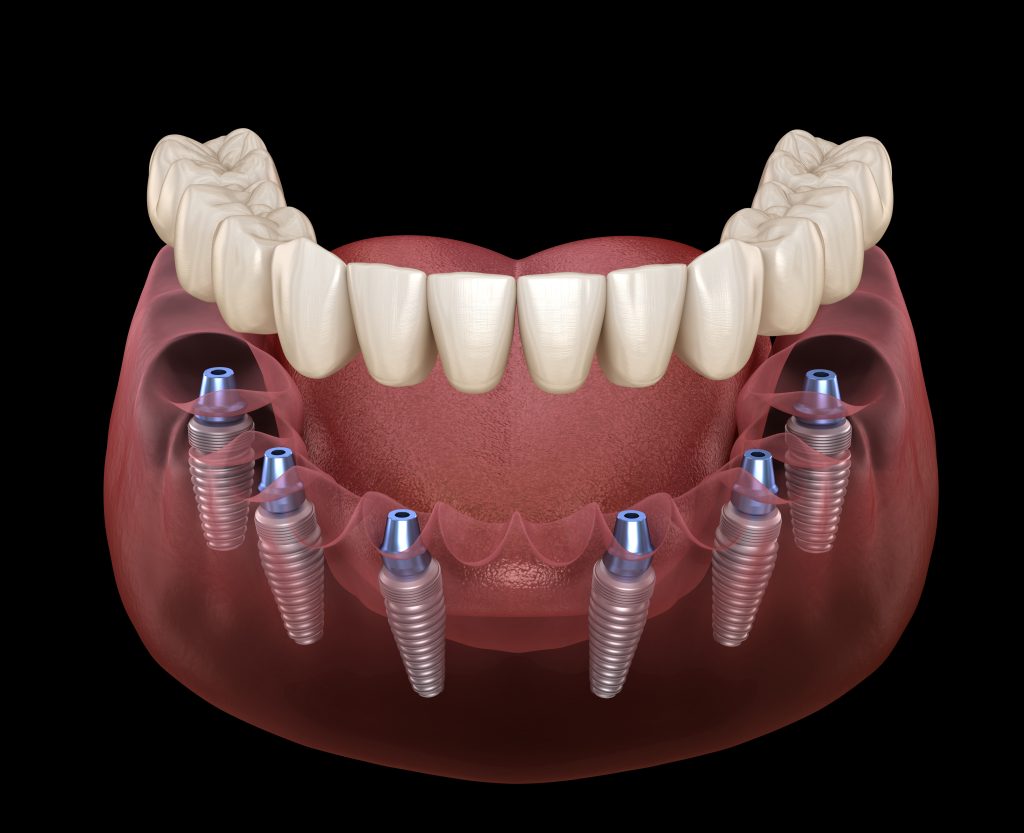

Advances In Dental Implantology